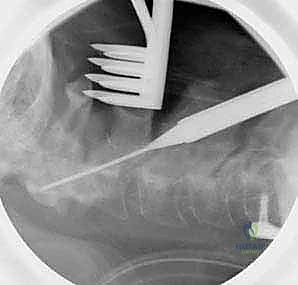

الخطوة 1: التخدير ووضعية المريض

يتم تخدير المريض تخديراً كلياً. ثم يُقلب المريض بعناية فائقة على بطنه (وضعية الانبطاح - Prone Position). يتم تثبيت الرأس باستخدام جهاز تثبيت الجمجمة ذو الثلاثة دبابيس (Mayfield clamp) لضمان عدم تحرك الرأس نهائياً أثناء الجراحة والحفاظ على محاذاة الرقبة.

الخطوة 7: التصوير الشعاعي داخل العمليات

طوال الإجراء، وخاصة بعد تركيب المسامير والقضبان، يتم استخدام جهاز الأشعة السينية المحمول (C-arm